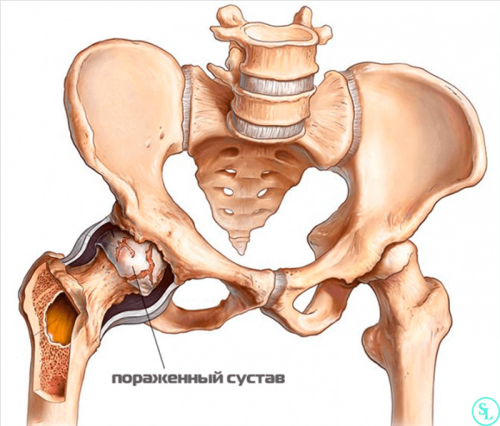

Рентгенография ТБС. Остеосинтез перелома устройствами <

• Асептический некроз головки

некроза головки бедра

в результате асептического

бедренной кости.